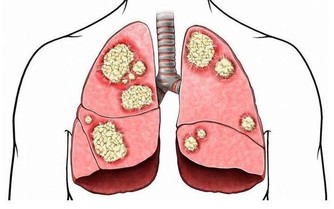

(1)嚴重的肝臟疾病

肝功能受損會導致凝血功能障礙,患者會出現全身各處都有淤青、出血點、破裂後傷口流血不止以及牙齦持續性出血等症狀。

肝臟是合成凝血因子的重要場所。肝供能受損,蛋白質的合成量會減少,相應的,凝血因子的合成量也會減少,這時候身體清除組織凝血活酶和被激活的纖溶因子的能力會下降,出現血液凝固功能障礙。